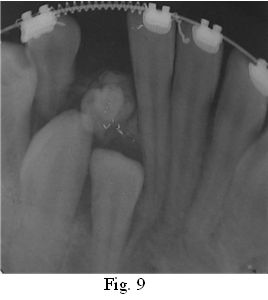

A los 2 meses de instalada la aparatología, se logra el espacio para ubicar correctamente el 4.3 y 4.2 en la arcada y se centra la línea media (Fig. 9), coordinándose en la Sección Quirúrgica de la Cátedra de Odontopediatría, la cirugía correspondiente para la enucleación del Odontoma Compuesto y la exodoncia del canino caduco (8.3). El acto quirúrgico constituye por lo tanto, un elemento más dentro de un plan de tratamiento integral y oportuno (Fig. 10).